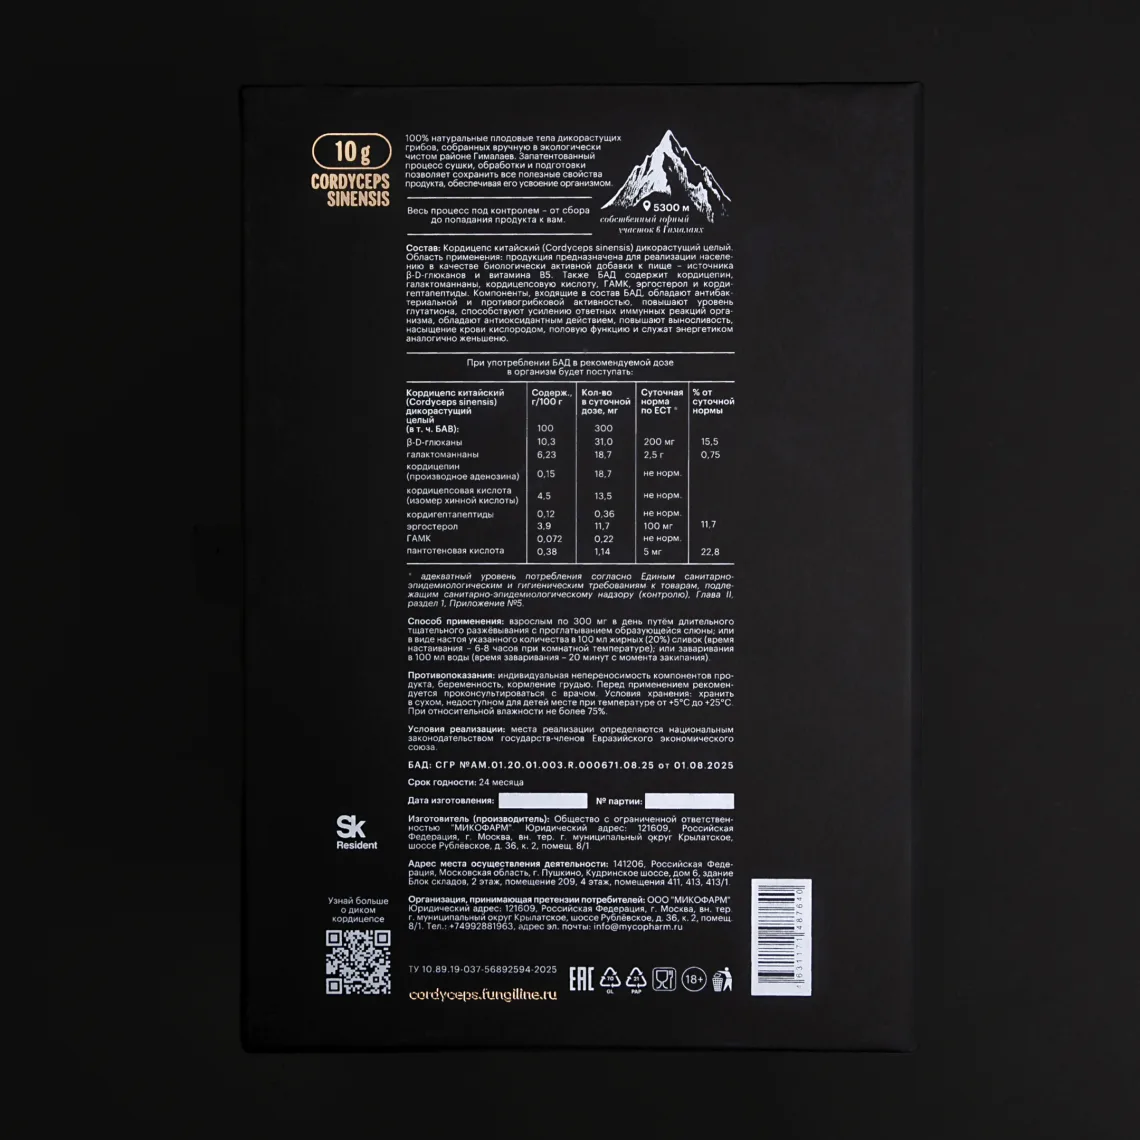

Дикий кордицепс (Ophiocordyceps sinensis) — редчайший гриб, известный как «тибетское золото». В традиции Китая он считался привилегией императоров и символом жизненной силы. В экстремальных условиях высокогорья он накапливает сильнейшие биоактивные соединения: кордицепин, аденозин, полисахариды, аминокислоты, ферменты и антиоксиданты. Эти компоненты обеспечивают мощный эффект: повышают выносливость, ускоряют восстановление, поддерживают иммунитет и гормональный баланс.

Инструкция:

- При высоких физических нагрузках, а также для повышения жизненных сил и бодрости — от 300 мг до 1 г в сутки путем длительного тщательного разжевывания с проглатыванием образующейся слюны. Возможен ситуативный, разовый прием до 3 г.

- При проблемах с потенцией — от 300 до 1.5 г в сутки ежедневного приема путем длительного тщательного разжевывания с проглатыванием образующейся слюны. Возможен ситуативный, разовый прием до 3 г.

Противопоказания:

- Индивидуальная непереносимость компонентов

- Беременность и период лактации

Состав

Кордицепс китайский (Ophiocordyceps sinensis) дикорастущий целый